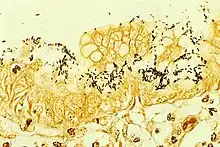

H. pylori can be demonstrated in tissue by Gram stain, Giemsa stain, H&E stain, Warthin-Starry silver stain, acridine orange stain, and phase-contrast microscopy. It is capable of forming biofilms. Biofilms help to hinder the action of antibiotics and can contribute to treatment failure.[30][31]